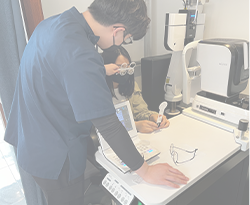

혁신적 검안 시스템

일반적으로 눈을 안경에 맞추는 것이 아닌, 임상 데이터를 기반으로 안경을 눈에 알맞게 맞추는 고도화된 검안 과정 도입

지속가능한 연구개발

수십년간 멈춰있는 검안 의료기술의 발전을 위해 XR, VR, 스마트 디바이스를 기반으로 새로운 검안 기술을 개발을 위해 노력